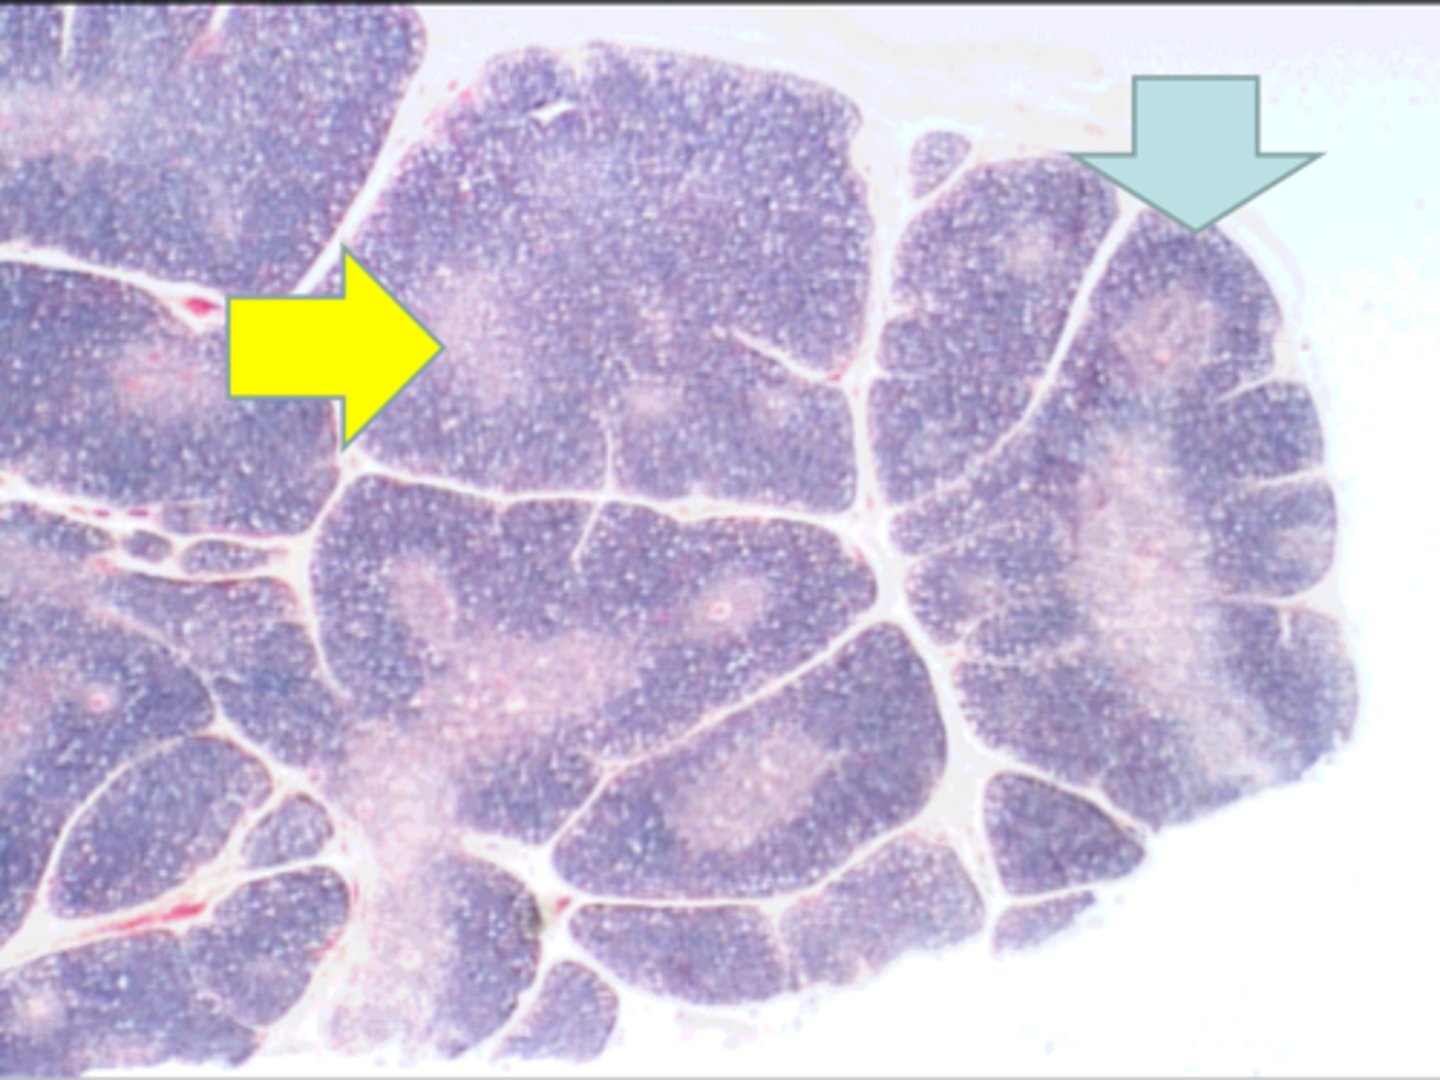

thymus

where is this tissue? thymus

yellow arrow

medulla containing T lymphocytes

blue arrow medulla containing T lymphocytes

Hassall's corpuscle

red arrow Hassall's corpuscle

Where is this tissue located? thymus